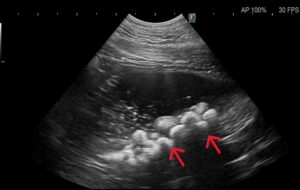

超音波検査上の結石